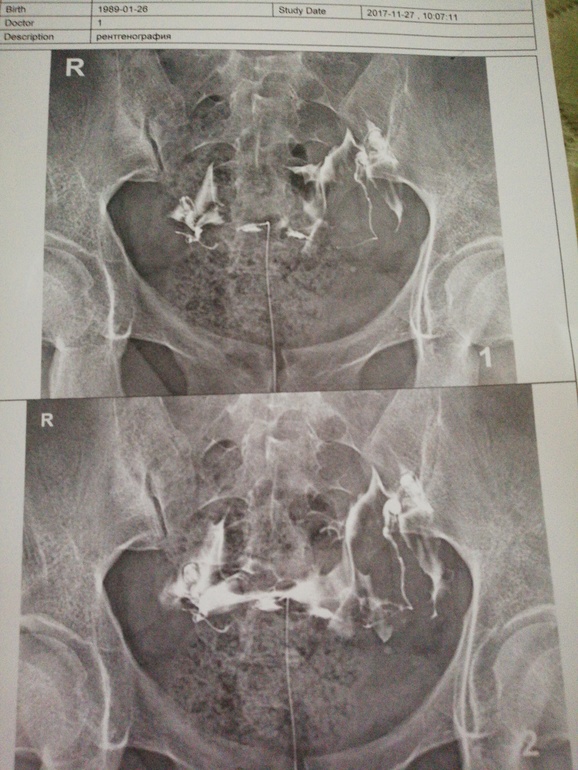

Привет всем. Мне назначили ранее рентген проходимости труб. Я боялась, но надо. У меня диагноз поликистоз яичников. Зашли мы в рентген кабинет мне поселили мною принесенное полотенце. (Делала в платной поликлиники. "Возраждение"Стоимость 5700 руб.) Легла на стол. Под попу подложили подушку. Вставили зеркало. Потом ввели катетер (не было ощущения ниаких) затем надула шарик какой-то таМ в матке ощущения тянущее в животе не более. Ввели жидкость (не чувствовала совсем) сделали снимок и ВСЕ!!! ЭТО СОВСЕМ НЕ БОЛЬНО. Девочки меньше читайте. И все зависит видимо от врача. Сейчас к вечеру просто немного тянет низ живота. Кстати обе трубы у меня замечательно проходимы. 😊 будем в след месяце делать отмену таблеток противозачаточных и пытаться забеременеть. УДАЧИ ВСЕМ.

Делали в кабинете где делают рентген. Меня когда положили все установили за 3 мин. Вышли врач с рентгенологом за дверь как обычно, и сделали снимок. Зашла врач ещё шприцом добавила в меня жидкости они опять выскочили за дверь, сделали ещё один снимок и все. С меня вынула катетер и маленький шарик резиновый который видимо там надували. Я встала оделась положила прокладку чтобы контрастное вещество лишнее вышло. И пошли мы в кабинет врача. Она смеялась с меня что я зря боялась. 😀

Жидкость видно на снимке разлилась в полости матки и труб. Очень хорошая проходимость.